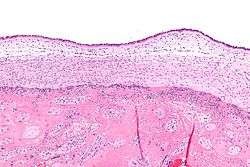

Micrograph showing chorioamnionitis. The clusters of blue dots are inflammatory cells (neutrophils, eosinophils and lymphocytes). H&E stain. | |

Chorioamnionitis can be diagnosed from a histologic examination of the fetal membranes.

Infiltration of the chorionic plate by neutrophils is diagnostic of (mild) chorioamnionitis. More severe chorioamnionitis involves subamniotic tissue and may have fetal membrane necrosis and/or abscess formation.

Severe chorioamnionitis may be accompanied by vasculitis of the umbilical blood vessels (due to the fetus' inflammatory cells) and, if very severe, funisitis (inflammation of the umbilical cord's connective tissue).